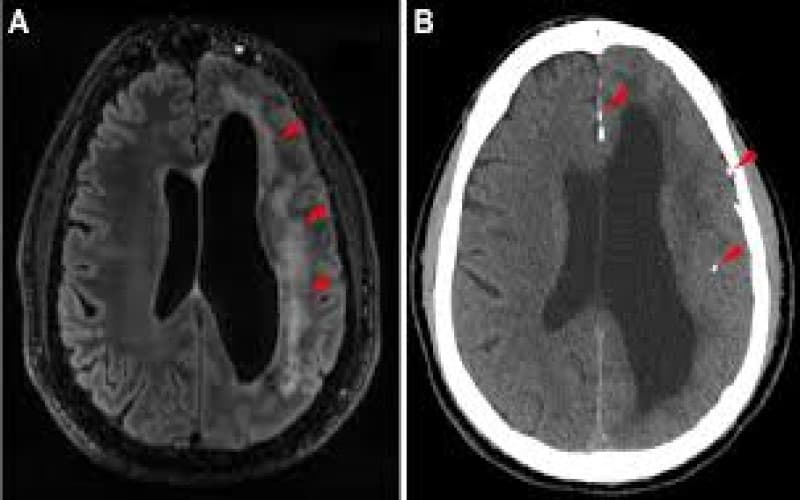

- Chụp cộng hưởng từ (MRI) não: đa số trường hợp có hình ảnh bình thường; tuy nhiên, một số bệnh nhân có thể ghi nhận tổn thương tại thùy thái dương, hải mã, thùy trán, thùy chẩm, nhân xám trung ương hoặc tổn thương vỏ và dưới vỏ não hai bên.